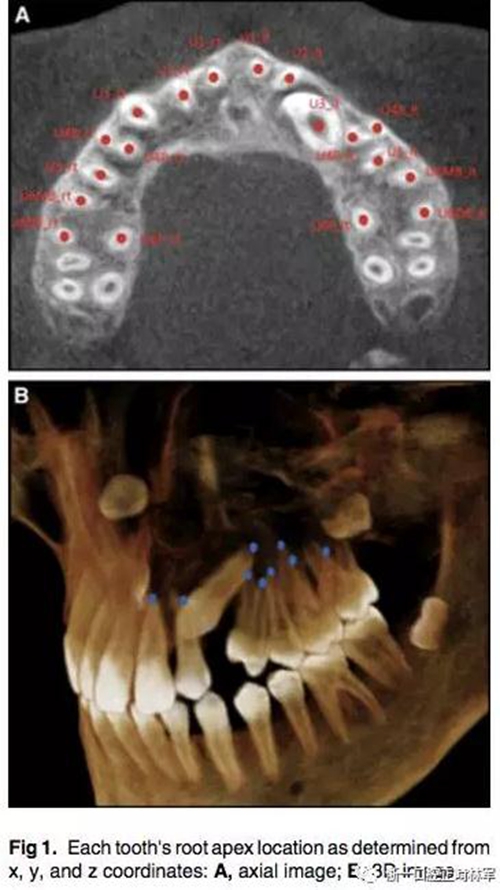

通過CBCT來確定尖牙牙根的具體位置,以x,y,z三維坐標表示。我們定義在面中線上,鼻根點作為鼻額縫在額骨上的最前點,CBCT掃描儀與腭平面水平。我們用3個標志點(前鼻棘點,兩側腭大孔的中心點)來定位腭平面,將鼻根點坐標定為(0,0,0),以此確定上頜牙齒根尖點的x,y,z的坐標。由于上頜前磨牙和磨牙有2-3個牙根,因此將多個牙根的中心點作為根尖點。見Fig1.

為了測量根尖與牙根弓形的偏移程度,必須先確定牙根的平均位置。然后,測量每個牙根與弓形的距離,對于阻生尖牙,它的牙根平均位置為對側非阻生尖牙對稱得到,測量阻生尖牙的牙根與對稱而來的牙根位置之間的距離。